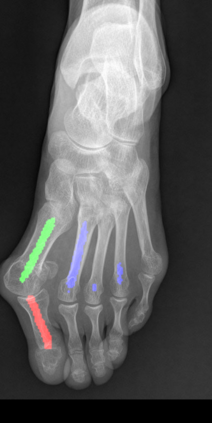

Angular measurements is essential to make a resonable treatment for Hallux valgus (HV), a common forefoot deformity. However, it still depends on manual labeling and measurement, which is time-consuming and sometimes unreliable. Automating this process is a thing of concern. However, it lack of dataset and the keypoints based method which made a great success in pose estimation is not suitable for this field.To solve the problems, we made a dataset and developed an algorithm based on deep learning and linear regression. It shows great fitting ability to the ground truth.